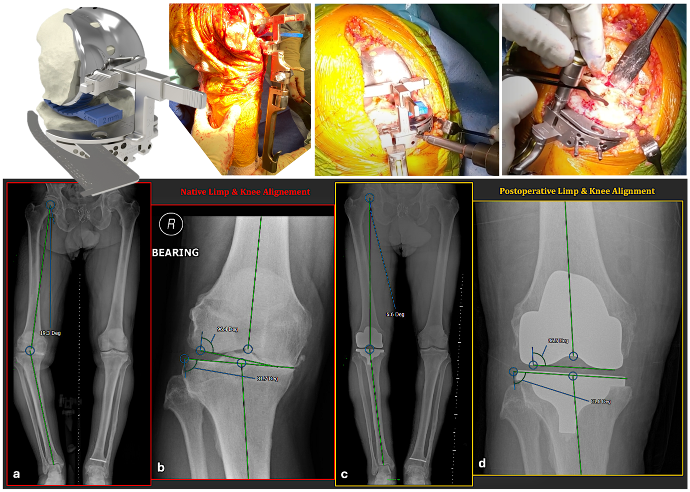

Zielsetzung und Fragestellung: Das uneingeschränkt kinematisches Alignment (KA) in der Knie Total-Endoprothetik (KTEP) bietet ein personalisiertes Vorgehen an, das die präarthritische konstitutionelle Anatomie des verschlissenen Knies wiederherstellt. KA ist weichteilfreundlich und mit verbesserten funktionellen Ergebnissen und höherer Patientenzufriedenheit verbunden. Eine der wichtigsten Säulen des Erfolgs bei der personalisierten KTEP ist die Genauigkeit & Präzision der Operationstechnik, damit ein physiologisch bilanziertes Gelenk ohne Weichteilreleases und Knochennachresektionen ermöglicht werden kann. Während Roboterassistierte KTEP in dieser Hinsicht Fortschritte zeigt, wird ihr tatsächlicher Nutzen angesichts der damit verbundenen erhöhten Kosten und Logistik in Frage gestellt. Diese Studie analysiert die Genauigkeit einer anwenderfreundlichen und standardisierten KA-Methode mittels Femur-basierter konventioneller Tibiavorrichtung.

Material und Methoden: Eine retrospektive Datenanalyse an 100 konsekutiven KA-KTEP wurde durchgeführt. Alle Patienten erhielten eine uneingeschränkte KA-Messschablonentechnik mit der Femur-basierten Tibiavorrichtung. Primärer Endpunkt war die Bewertung der Genauigkeit bei der Wiederherstellung der femoralen und tibialen Ausrichtungswinkeln, LDFA and MPTA. Der sekundäre Endpunkt wertete die Inzidenz von intraoperativen Nachresektionen an der Tibia aus. Eine Reliabilitätsanalyse (ICC) der LDFA and MPTA auf Röntgen (Ganzbeinaufnahme) wurde ebenso durchgeführt, um den Bias Effekt zu bewerten.

Ergebnisse: 50 Patienten mit geeigneten präoperativen und postoperativen Ganzbeinaufnahmen wurden für die Genauigkeitsanalyse eingeschossen. Die mittlere Abweichung von LDFA und MPTA betrug -0,17° ±1,0° (-2,6 – 2,1°) und 0,46° ±2,2° (-3,7 – 6,5°). Die ICC-Reliabilitätsprüfung der Röntgenmessungen zeigte insgesamt eine „almost perfect“ Übereinstimmung (0,97 – 0,98), mit einer „substantial“ Übereinstimmung bei den schwereren Valgus-Phänotypen >10° (0,79 – 0,92). Bei einem anfänglichen Tibiaschnitt von 10 mm unter Verwendung des „Linked-Jig“ Geräts betrug die Nachschnittrate 23%, wovon nur 5% auf eine Orientierungskorrektur der Koronal- oder Sagittalebene entfielen.

Diskussion und Schlussfolgerung: Die Verwendung der „Linked-Jig“ Technik kann zuverlässig und mit hoher Genauigkeit die Anatomie des konstitutionellen Knies wiederherstellen. Der vorgegebene 10 mm initiale Resektionstiefe der Tibia unter Verwendung dieser Schablone erzeugt möglicherweise nicht genügend Gelenkspaltraum für physiologische Weichteillaxität.

Abbildung 1 [Abb. 1]